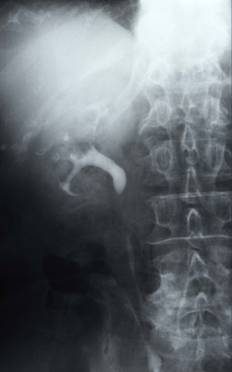

③逆行性性腎盂・尿管造影

膀胱鏡下にカテーテルを腎盂まで挿入し造影検査をしたり、細胞診の検査のために腎盂内の尿を採集します。